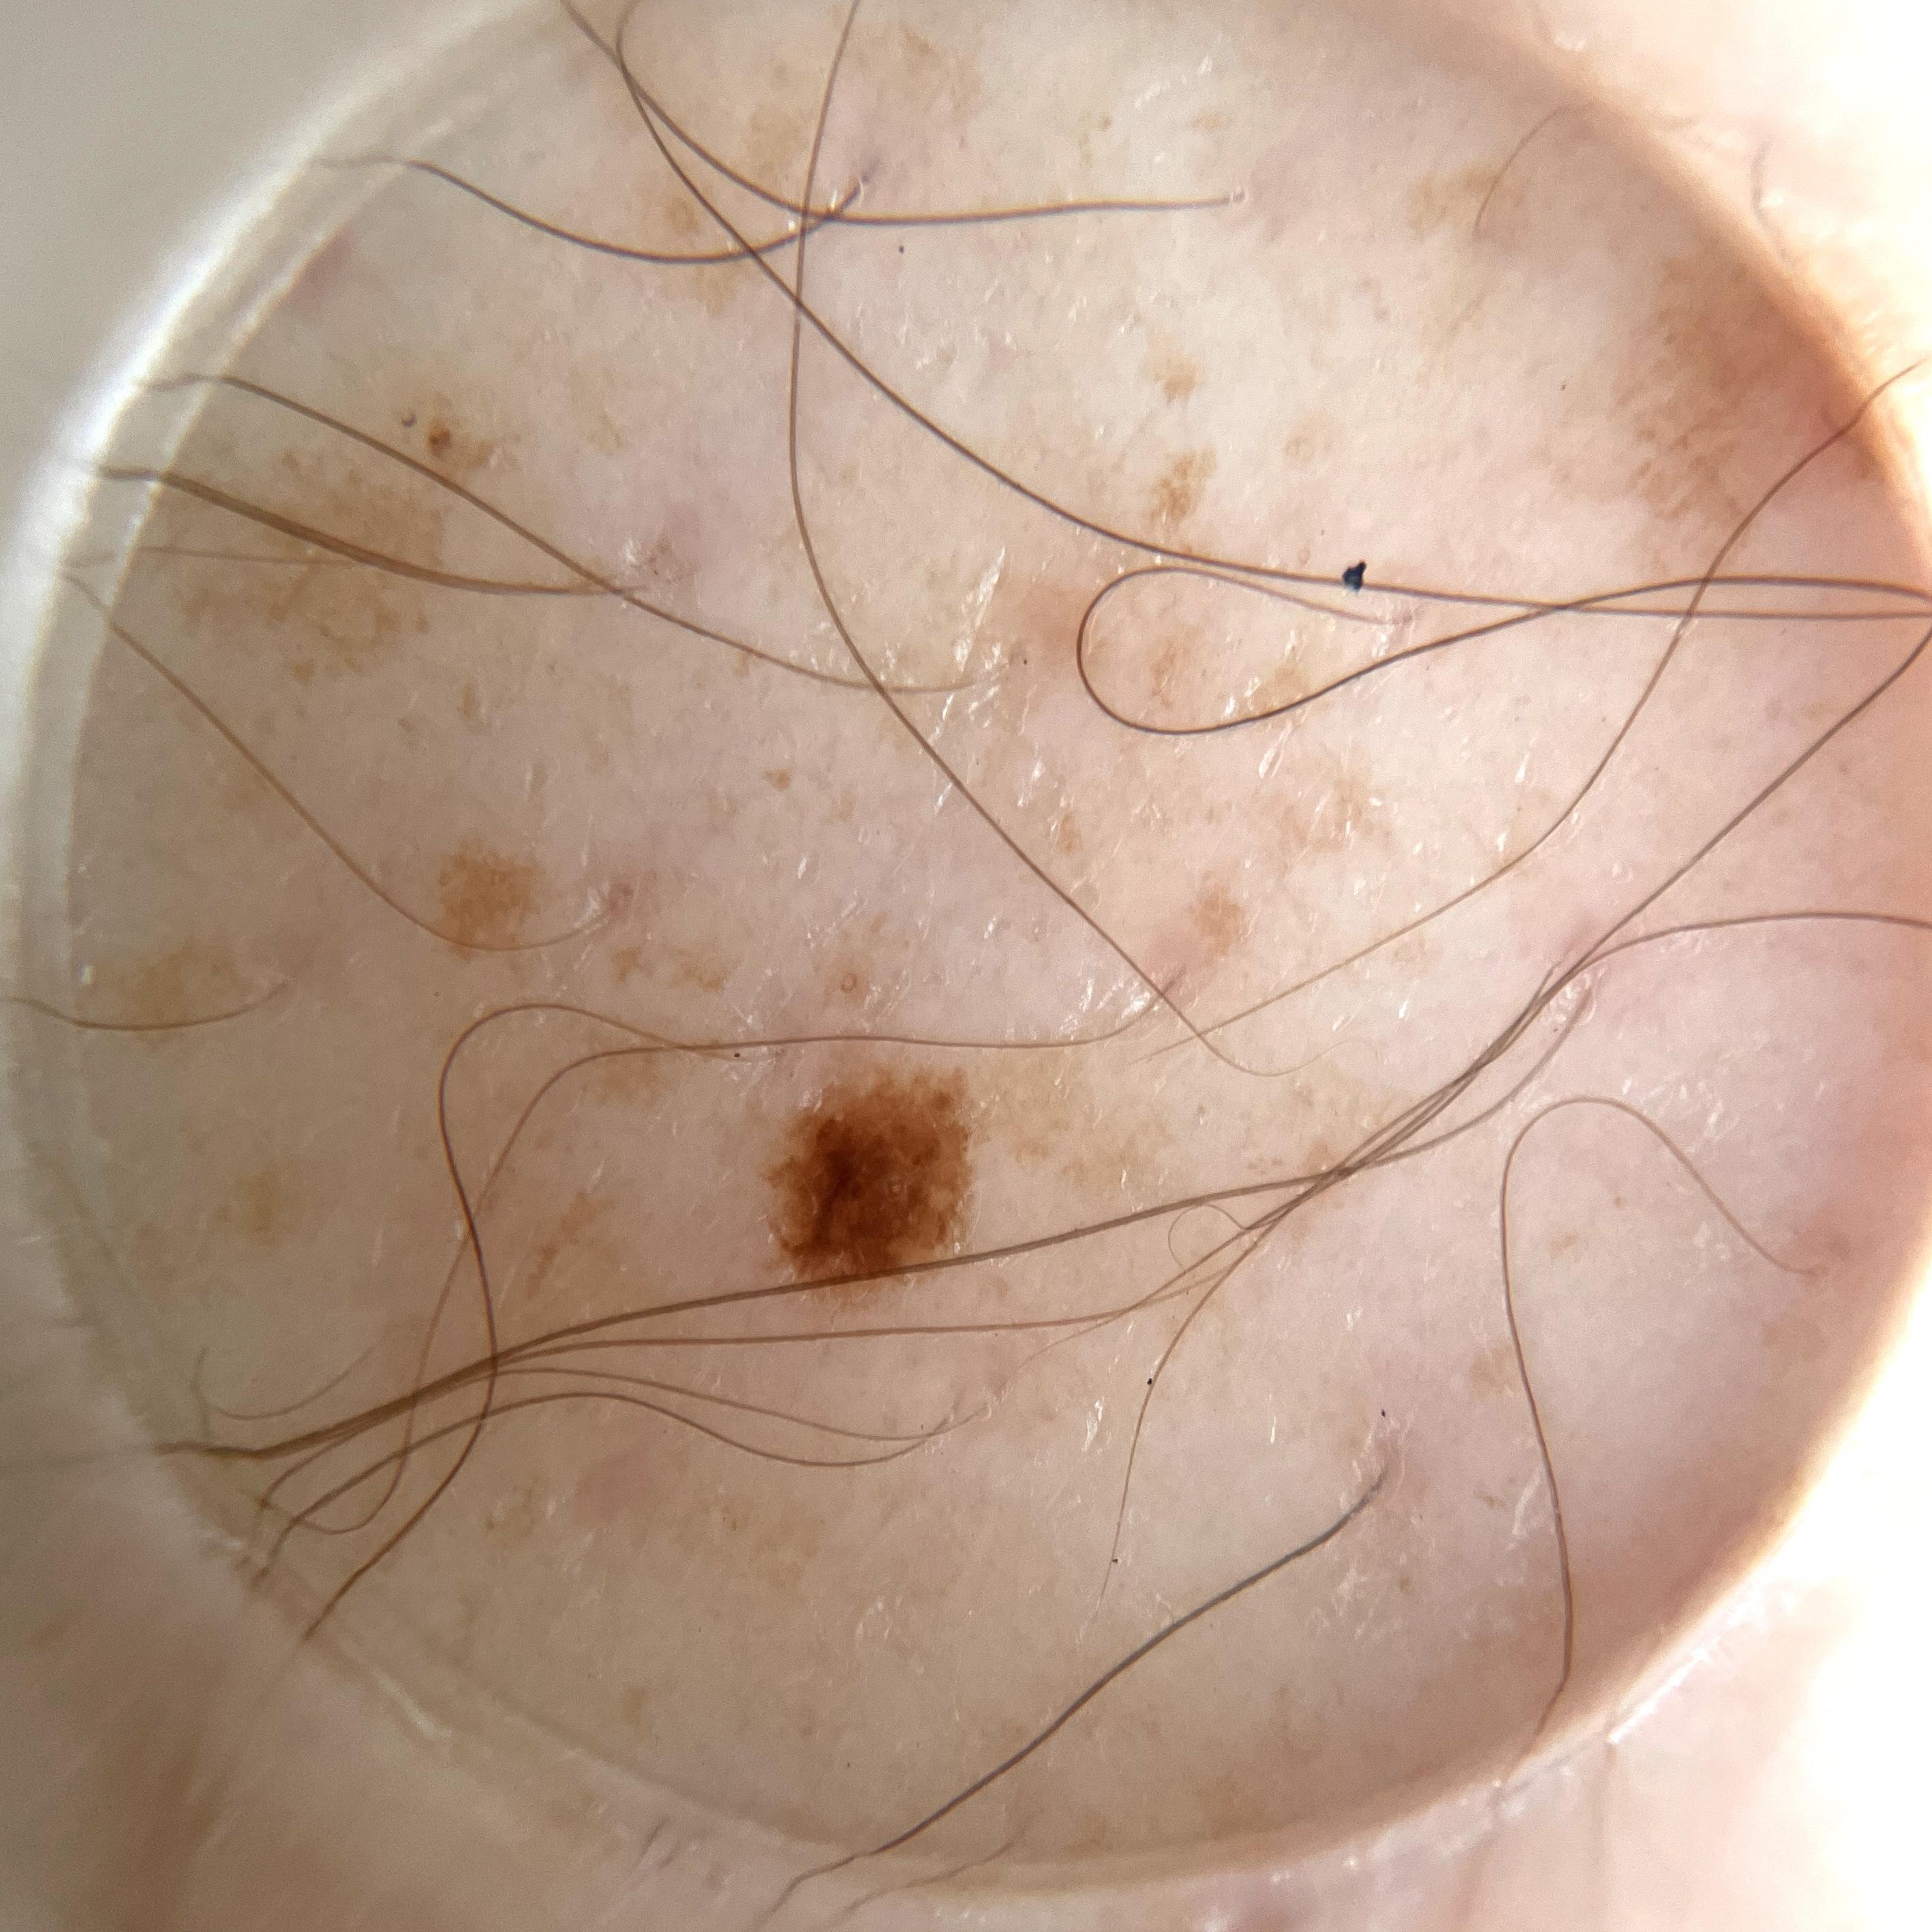

ISIC_5706752

Clinical

Field Value

acquisition_day 264

age_approx 55

anatom_site_1 Lower extremity

anatom_site_general lower extremity

concomitant_biopsy False

diagnosis_1 Benign

diagnosis_confirm_type single image expert consensus

family_hx_mm False

fitzpatrick_skin_type I

image_manipulation instrument only

image_type dermoscopic

lesion_id IL_0266048

patient_id IP_7932723

personal_hx_mm True

sex male